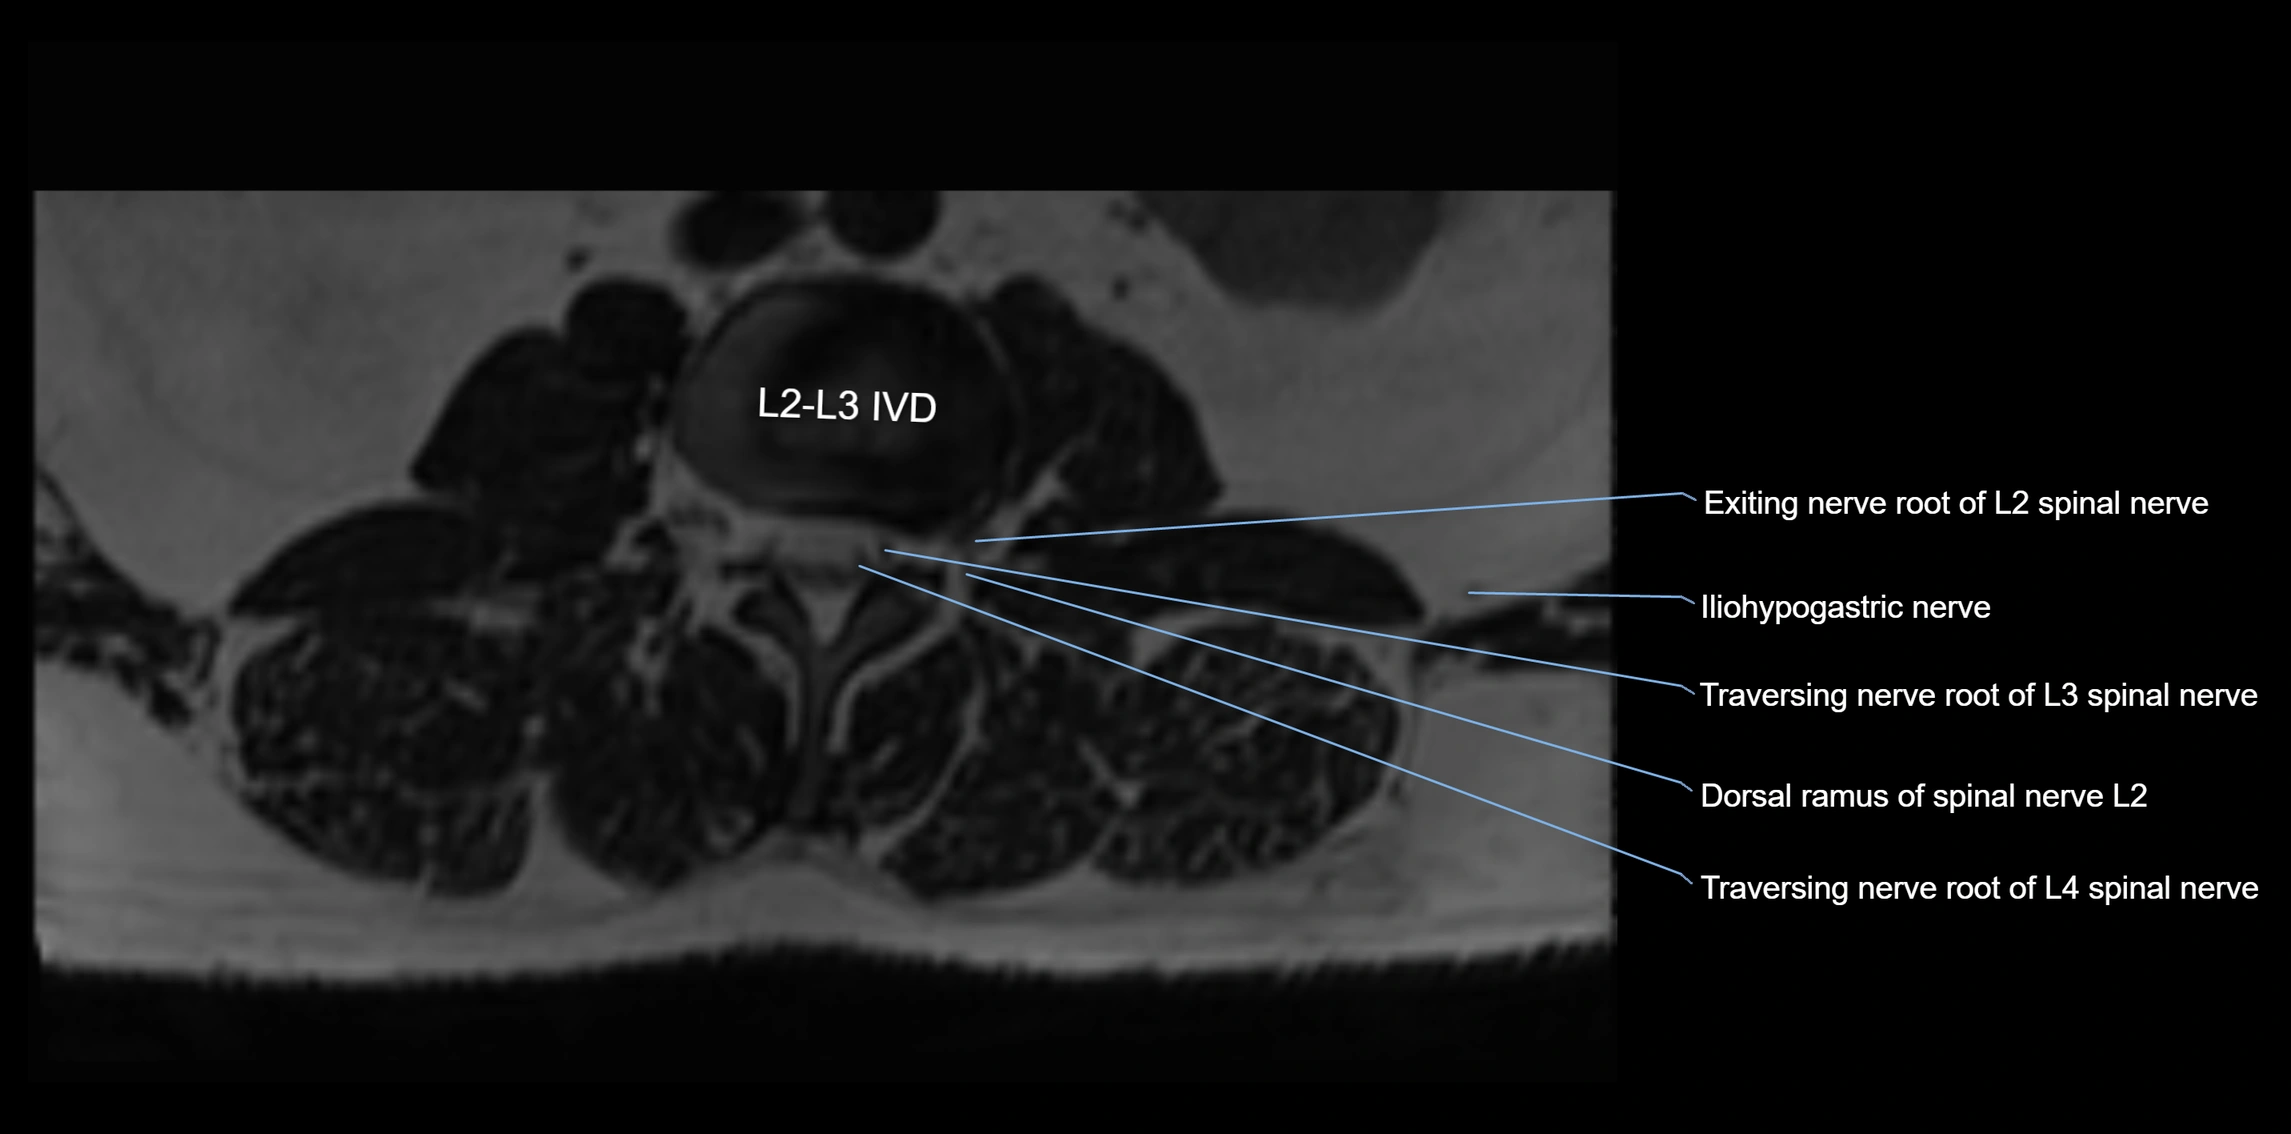

MRI image

image